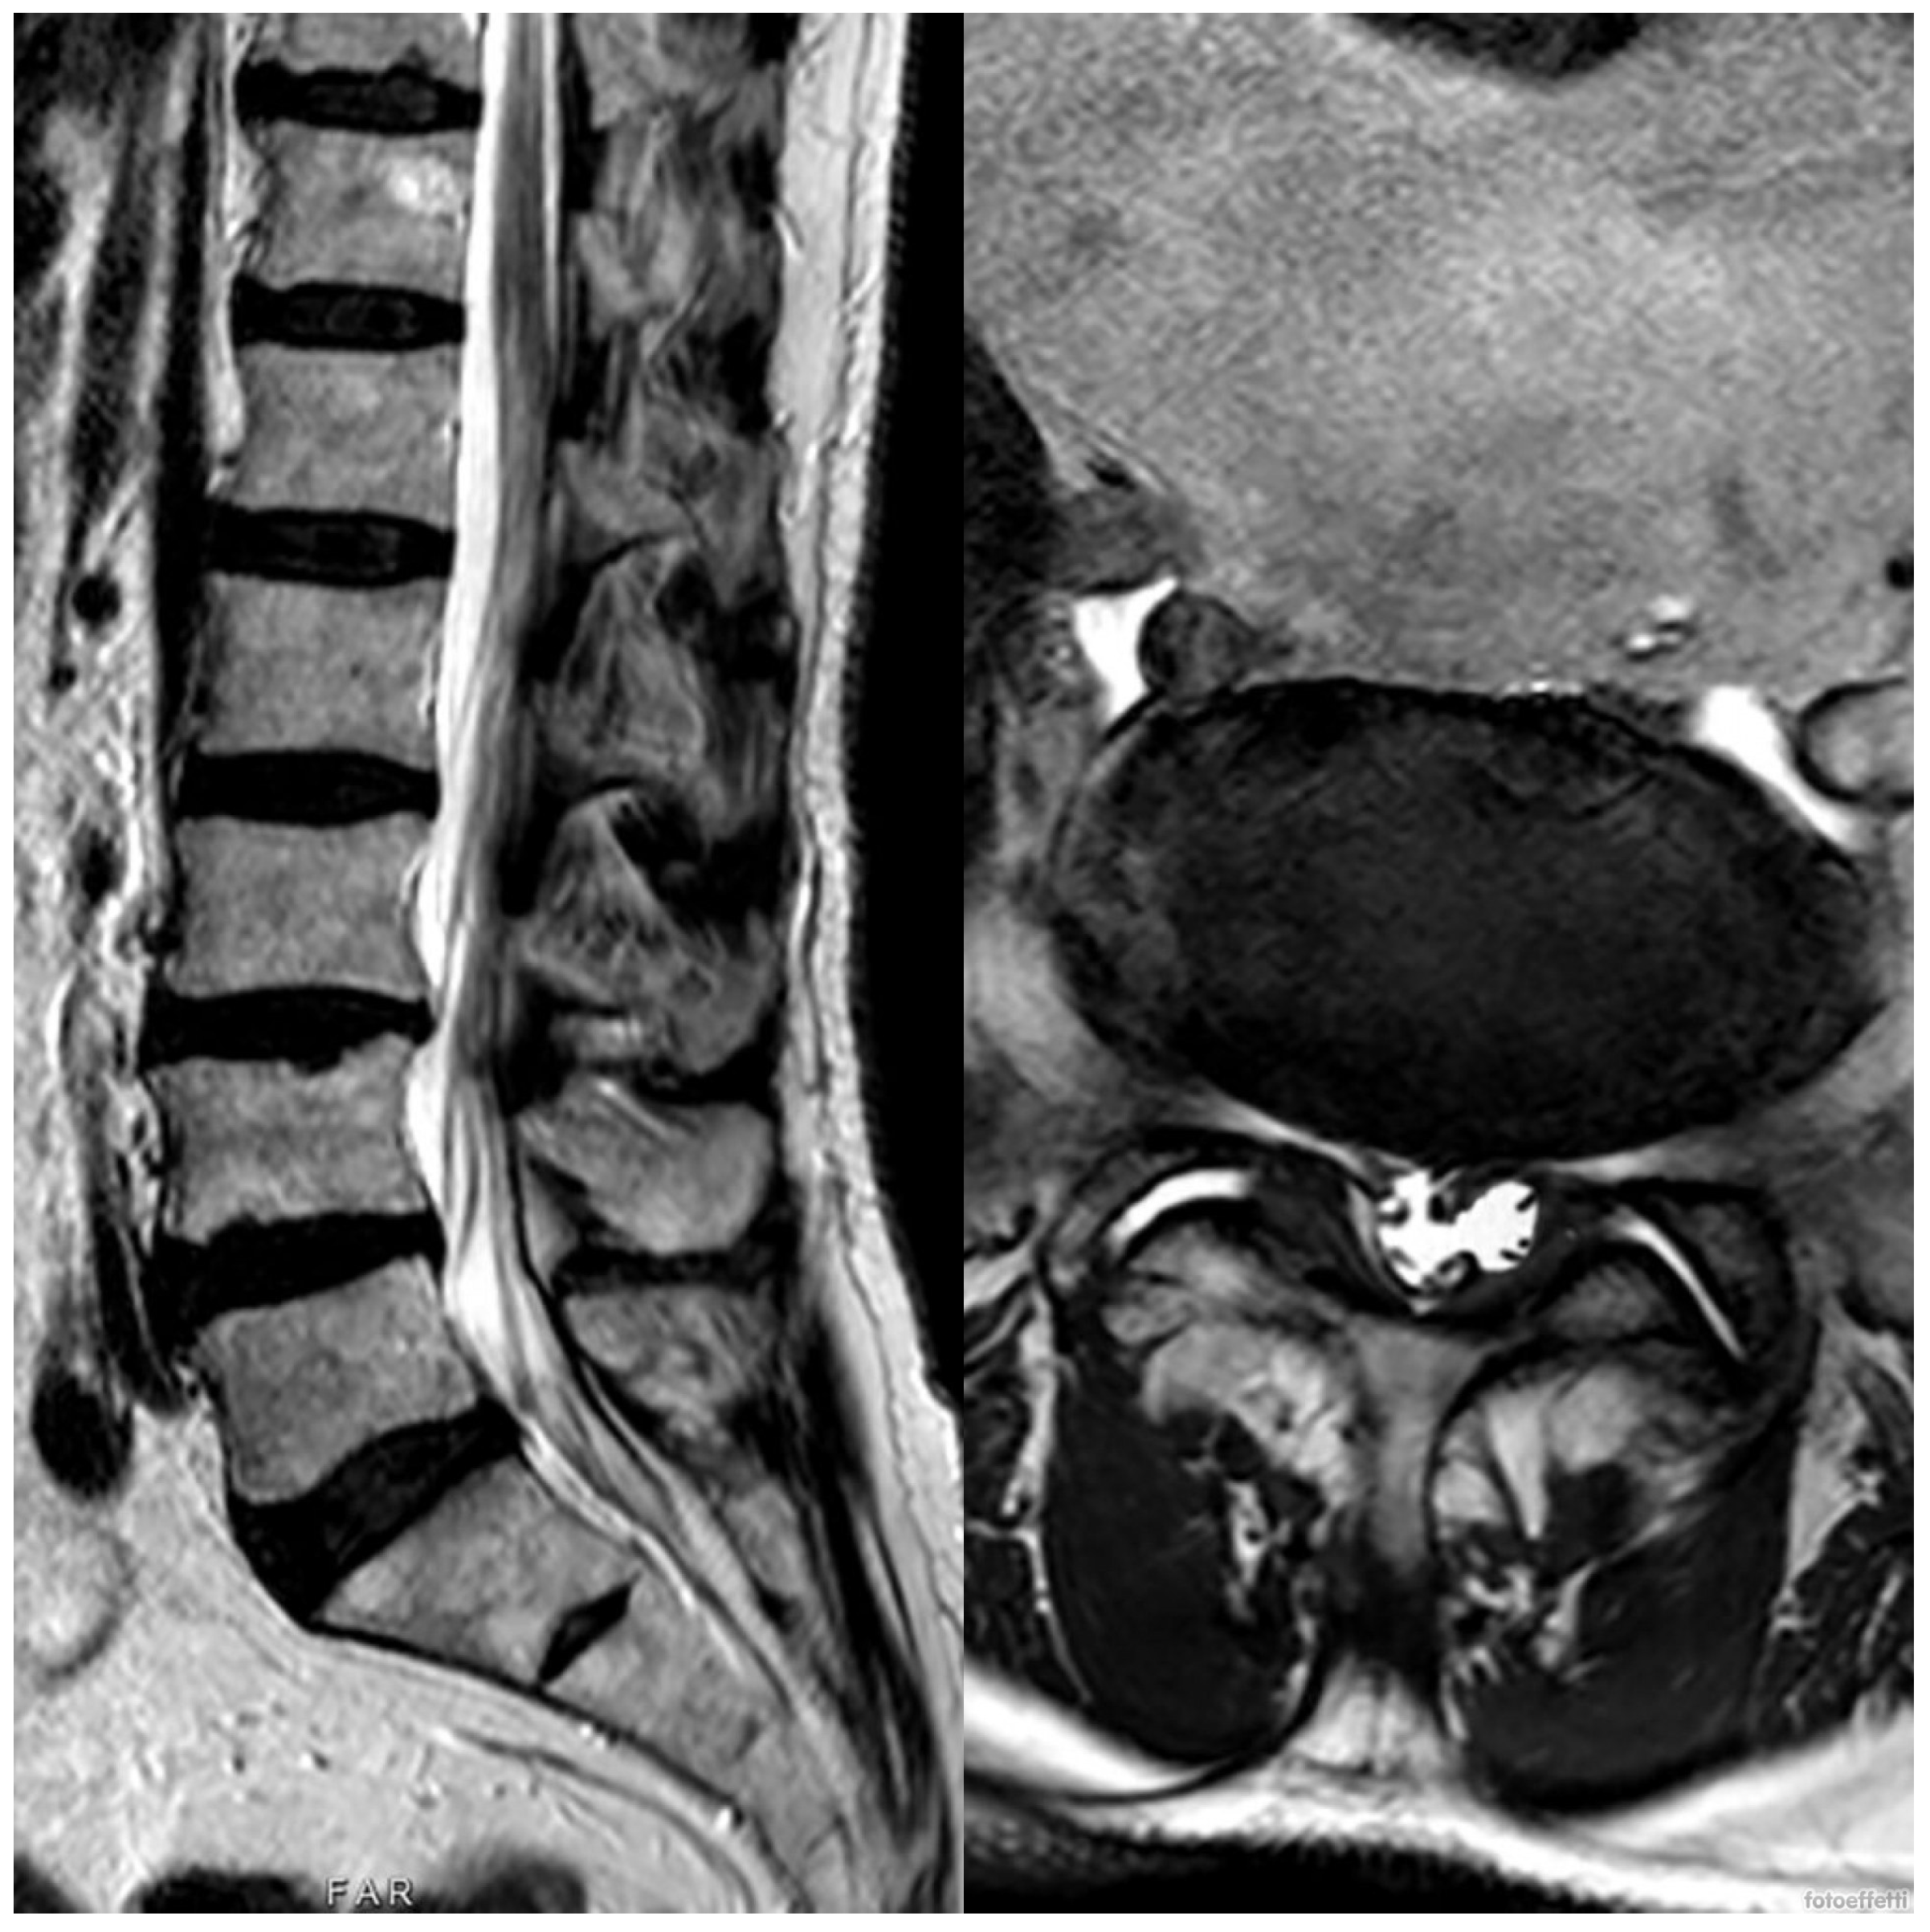

2. Case Presentation